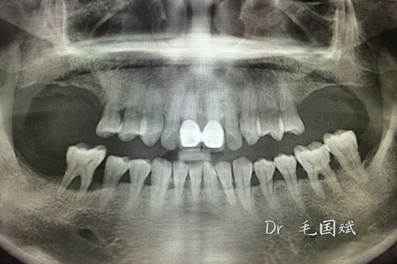

毛國(guó)斌種植病例——群討論分享